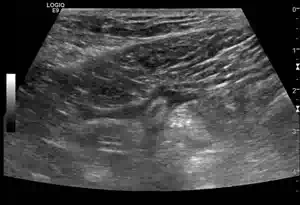

Längsschnitt über der Gallenblase

Lageverschieblichkeit zweier Gallenblasenkonkremente mit akuter Cholezystitis

Im Längsschnitt über die Gallenblase erkennt man auf dem linken Bild neben einer verdickten Gallenblasenwand zwei Konkremente, die sich am Ausgang der Gallenblase, dem sogenannten Infundibulum (lat. Trichter), befinden. Lässt man den Patienten aufstehen, wie rechts im Bild dargestellt, fällt eines der Konkremente der Schwerkraft folgend in den Fundus der Gallenblase, während das zweite weiterhin im Infundibulum eingeklemmt bleibt.

Da die Gallenblase auch ohne Zufluss aus der Leber ständig Sekrete in ihr Lumen absondert, steigt bei einem blockierten Ausgang der intraluminale Druck kontinuierlich an. Steigt der Druck in der Gallenblasenwand, kollabieren zunächst die venösen Gefäße. Bei weiterhin bestehendem arteriellem Zustrom fällt dadurch der venöse Abfluss aus, was zu einer zunehmenden Kongestion und weiteren Wandschwellung führt.

Mit fortschreitender Druckerhöhung wird schließlich auch der arterielle Perfusionsdruck erreicht, wodurch auch die Arterien komprimiert werden. Ab diesem kritischen Punkt ist die Gallenblase vollständig von der Blutversorgung abgeschnitten und es entwickelt sich eine ischämische Nekrose der Gallenblasenwand. Unbehandelt kann dies zu Perforation, Peritonitis und septischen Komplikationen führen, weshalb die frühzeitige sonographische Diagnose und rechtzeitige Intervention von entscheidender Bedeutung sind. Die dargestellte fehlende Lageänderung eines der Konkremente bei Positionswechsel ist  daher ein wichtiges diagnostisches Zeichen zum Beweis einer Obstruktion des Infundibulums